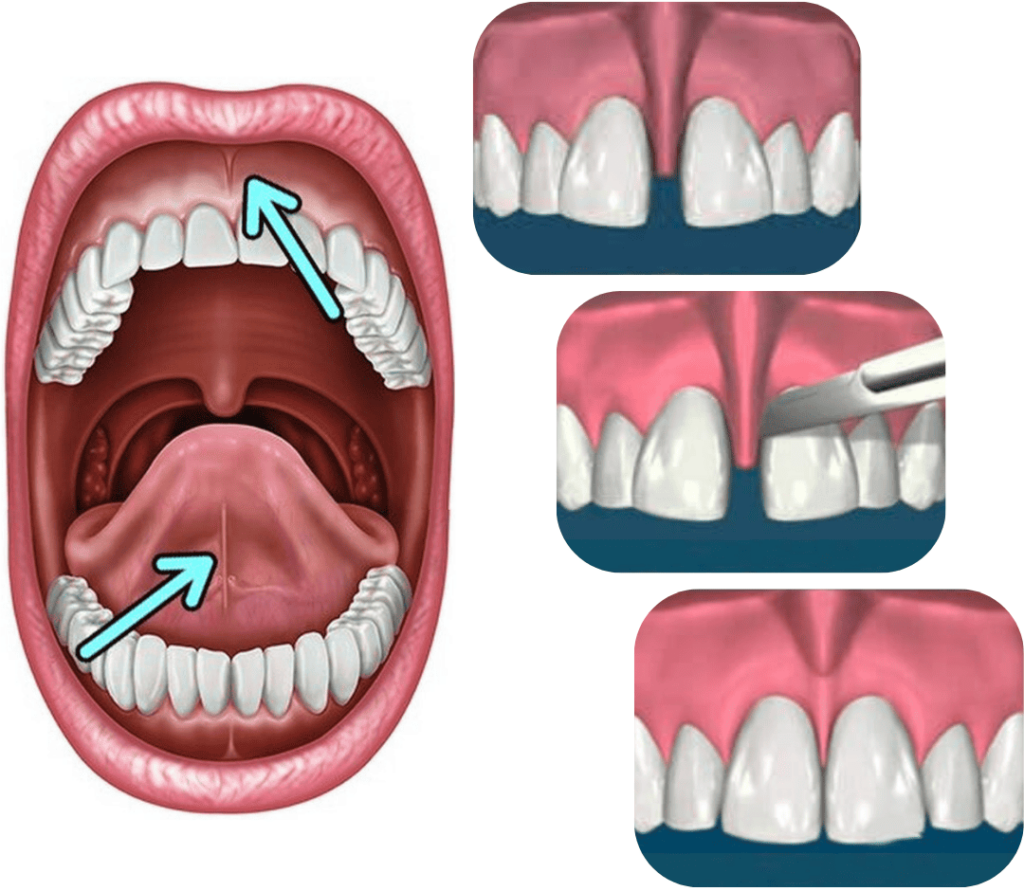

FRENULEKTOMIJA

Frenulektomija je oralno-kirurški zahvat kojim se oslobađa frenulum – resica koja se nalazi ispod gornje usne ili ispod jezika.

Frenulum u donjoj čeljusti može ograničavati pokretljivost jezika i otežavati govor, dok u gornjoj čeljusti može uzrokovati razmak između prednjih zuba (dijastemu) ili povlačenje zubnog mesa.

Zahvat je jednostavan, bezbolan i traje kratko.

Zahvat se radi pod lokalnom anestezijom, a oporavak je brz i bezbolan.